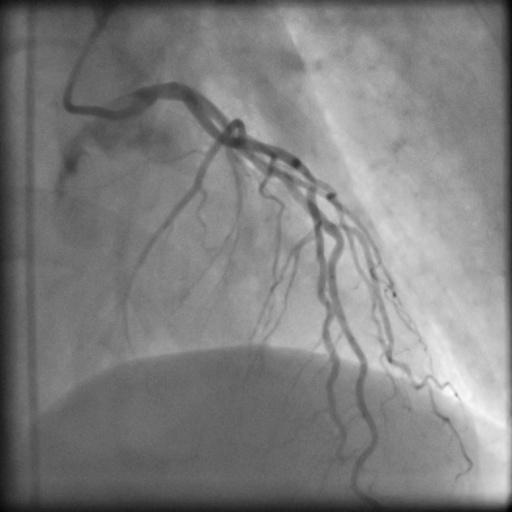

| Image | Ground truth | Video frame | Ground truth | Video frame | Ground truth |

| XCAD [33] | CADICA [19] | Our XACV dataset | |||

4.1 XACV Dataset

We collect 111 complete records of coronary artery X-ray videos, encompassing the injection, flow through the blood vessels around the heart, and dissipation of the contrast agent. Subsequently, we establish the XACV (X-ray Angiography Coronary Video) dataset. Each video consists of varying numbers of high-resolution coronary artery X-ray images. We invite experienced radiologists to annotate the vascular regions, focusing on one or two frames where the contrast agent is most prominent in each video. The XCAD dataset contains only a single image, and the CADICA video dataset does not provide corresponding ground truth. Therefore, in the following experiments, we conduct all the analyses on our collected XACV dataset and the corresponding GT for each sequence. In Figure 5, we show that compared to other publicly available datasets, XCAD [33] and CADICA [19], our dataset exhibits finer annotations in the vascular regions, providing an advantage for future related tasks. The development and use of our dataset have been approved by our institution’s IRB.